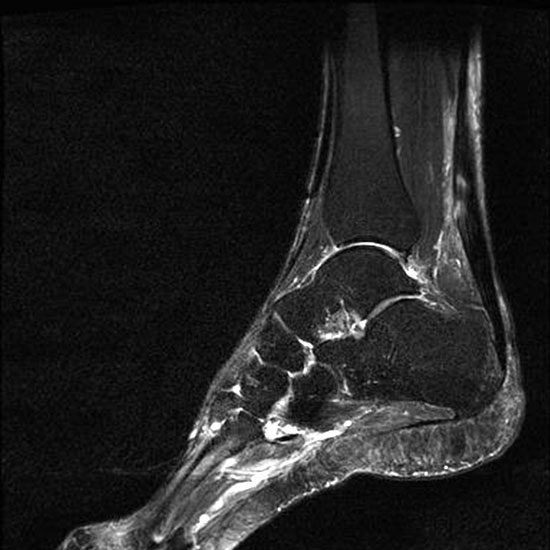

Hier befindet sich ca. 3-5 cm proximal des Tuber calcanei ein als „kritische Zone“ benannter Bezirk, der durch eine ungünstige arterielle Blutzufuhr gekennzeichnet ist (letzte Wiese). Hier finden sich häufig spindelförmige Schwellungen, die bei MRT-Diagnostik nicht selten partielle Nekrosen und Partialrupturen der Achillessehne aufweisen (Abb. 14).

Unabhängig davon können insbesondere chronische Insertionstendinosen der Achillessehne von Partialrupturen (Abb. 15) und erosiven Läsionen des dorsalen Fersenbeines begleitet sein.

Die sonographische Diagnostik eignet sich primär zur Erkennung schmerzhafter Prozesse im Verlauf der Achillessehne und kann bei Bedarf durch Röntgen bzw. MRT ergänzt werden. Besonders bei längeren Verläufen und kräftigen spindelförmigen Schwellungen (>9mm, Normwert <5mm) im Bereich der kritischen Zone sollte ein MRT zum Ausschluss von Nekrosezonen und Partialrupturen vor Therapiebeginn veranlasst werden. Die sonographisch leicht zu erfassende Veränderung der Sehnendicke im mittleren Sehnenanteil ist ein guter Indikator für die Schwere der Erkrankung und die Beurteilung des Behandlungsverlaufes. Die sichtbaren Veränderungen am distalen knöchernen Ansatz der Sehne sind diskreter.

Insbesondere bei größeren Partialrupturen (Abb. 14) sollten operative Verfahren erörtert werden. Kleinere Partialrupturen sind der ESWT gut zugänglich, wie die beiden nachfolgenden Beispiele zeigen: